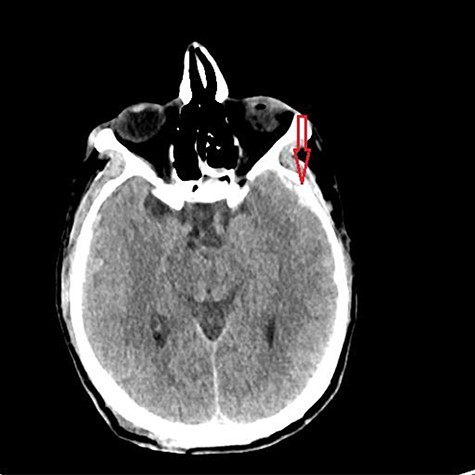

A 59-year-old male was found in the street with a head laceration. He was brought to the trauma bay as a pedestrian struck trauma patient with a prehospital GCS of 3. On arrival, his GCS was 11 (E3, V2, M6). An expanding neck hematoma was seen on exam. CT scan revealed scattered bilateral frontal contusions with hemorrhage in right basal ganglia, small bilateral acute SDH without significant mass effect, minimally displaced right temporal/occipital skull fracture and right-sided rib fractures 1–7 (flail chest) with hemopneumothorax (Fig. 1).